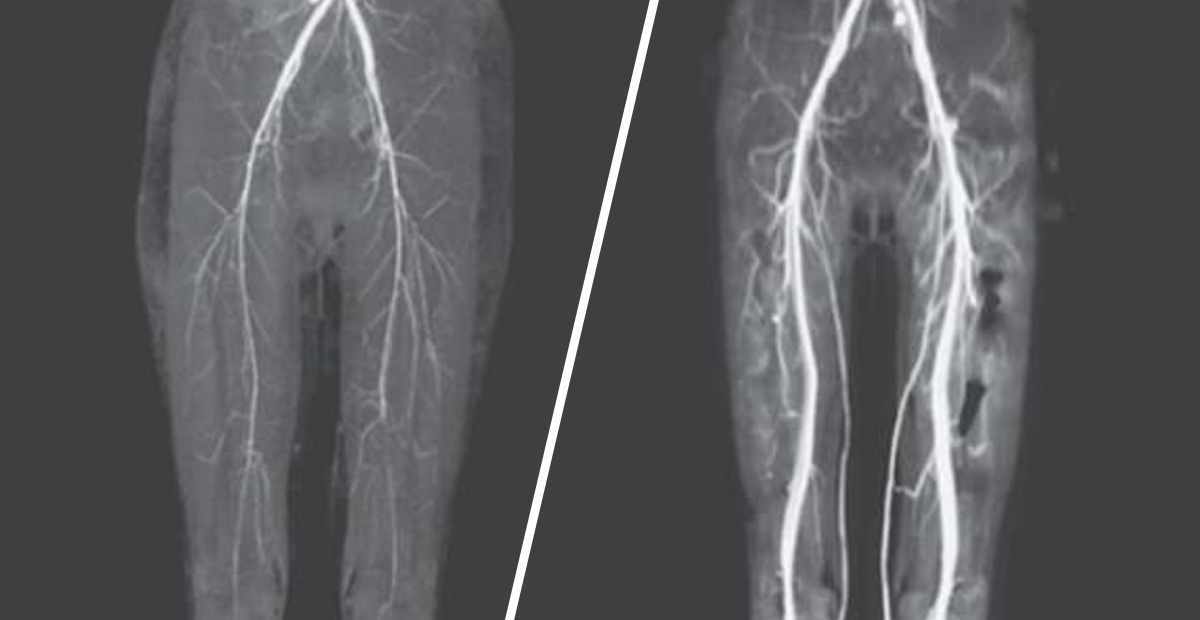

As it turned out, she was diagnosed with St. Anthony’s fire or Holy Fire – a medieval disease caused by ingesting ergot. According to iflscience.com, when the patient was examined, she was found to have extremely cold legs and two of the main arteries in the legs were on the verge of collapse.

She was given a blood thinner which increased the flow of blood though her arteries but because of gangrene she lost one toe. Ergotamine was used in the 1500s to induce childbirth and today is used in treating migraines and cluster headaches.

The patient was taking Ergotamine for migraines and it interacted with another medicine she was taking for HIV causing the problems in her legs.